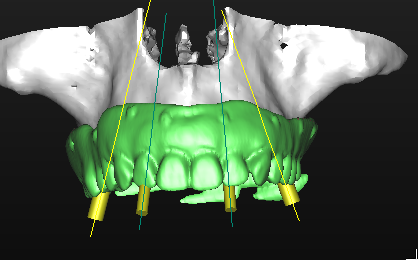

La pianificazione con Simplant permette l’accoppiamento tra la protesi e i tessuti molli oltre alla corretta valutazione della posizione, dell’inclinazione e dell’orientamento tridimensionale degli impianti (Figg. 15-17). Questo tipo di progettazione consente di eseguire una procedura chirurgica protesicamente guidata, sfruttando l’emergenza degli impianti nella loro più ideale posizione, con benefici dal punto di vista protesico e biomeccanico (Figg. 18, 19)

Grazie a questo tipo di pianificazione il software produce una guida chirurgica che viene stampata da una stampante 3D e consente al chirurgo di operare con tecnica “flapless” cioè senza la necessità di aprire dei lembi e causare un maggiore traumatismo al paziente. La guida chirurgica trasparente viene provata in bocca al paziente prima dell’intervento chirurgico per testare la sua stabilità e precisione nel rapporto con i tessuti molli (Figg. 20, 21). In questo caso specifico si era pianificato di utilizzare un nuovo approccio con degli impianti e componenti protesiche particolari, la tecnica “Smart fix” di Astra Tech Implant (Dentsply Sirona) (Figg. 22-25).

I due impianti più posteriori (Astra Tech Implant System EV, Densply Sirona) hanno un design particolare, sono disegnati con un profilo diverso dal normale, con un collare anziché piatto inclinato in maniera tale da consentirne il posizionamento con un asse ed un’angolazione antero posteriore, adattandosi così nella loro emergenza alla cresta ossea (Fig. 22). I due impianti anteriori soni impianti standard, in questo caso con diametro 3,5 mm (Fig. 23). La componentistica protesica prevede MUA (multi unit abutments, multibase Dentsply Sirona) standard sui due impianti anteriori (Fig. 24) e due MUA angolati componibili ed orientabili sui due impianti posteriori (Fig. 25).